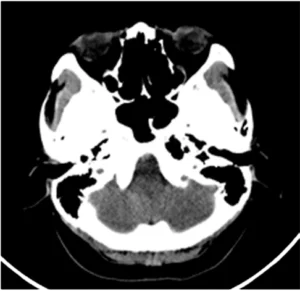

• Bietet Kunden einen 128-Zeilen-CT mit einer großen 76 cm Apertur

und verbessert die Bildauflösung auf 21 Lp/cm, was zu einer

genauen Krankheitsdiagnose und -behandlung beiträgt und

die klinische Leistungsfähigkeit und Erweiterbarkeit des Geräts erheblich verbessert.

• 64-Zeilen-/40-mm-Detektor

» 64 × 0,625 mm äquidistantes Array

» Hohe Effizienz

» Äquidistanter Detektor